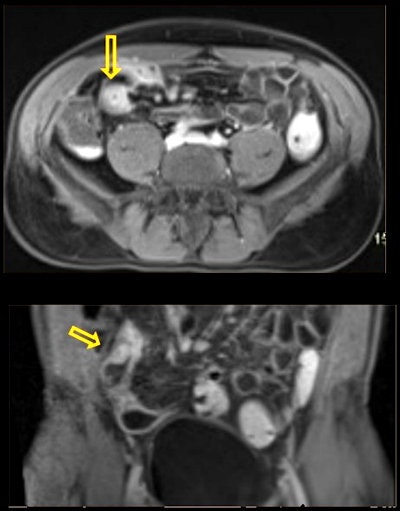

58-year-old man with a history of diffuse abdominal pain. Incidental finding on prostate screening: ileal wall thickening and increased mural contrast enhancement, suspicious of intestinal inflammatory disease. Crohn's disease was confirmed posteriorly. All figures courtesy of Dr. Eduardo Alvarez-Hornia Pérez.It is important that radiologists look beyond the prostate and accurately recognize and characterize incidental findings, differentiating indolent entities from clinically significant pathologies and avoiding error in diagnosis and treatment, Alvarez-Hornia and colleagues noted in an e-poster presented at ECR 2021.